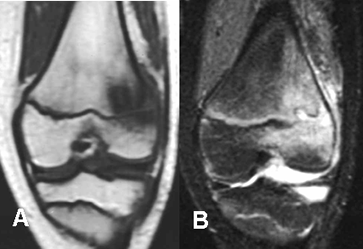

Fig 35. Osteomielitis.

A: RM coronal en T1 y B: RM coronal en STIR. Edema óseo en la región metafiso-epifisiaria distal del fémur, con cambios inflamatorios en los tejidos blandos, por osteomielitis.